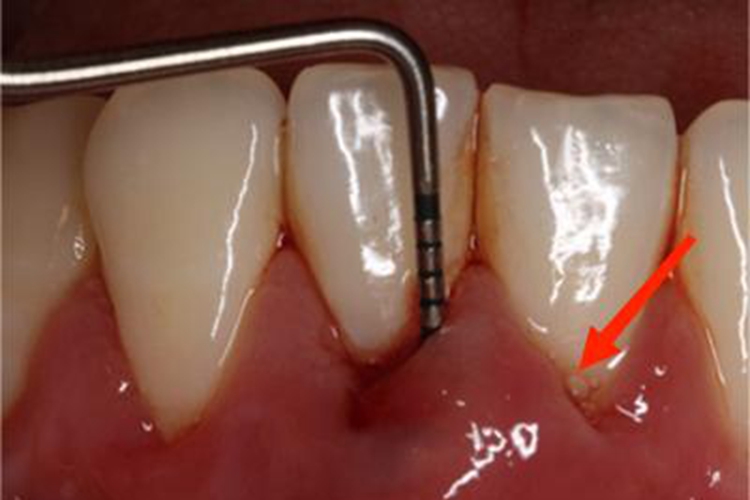

发病突然,牙龈形成椭圆形或半球状的肿胀突起,牙龈发红、水肿,表面光亮,早期疼痛明显,患牙有“浮起感”,叩痛,松动明显。后期脓肿表面较软,扪诊可有波动感,疼痛稍减,轻压牙龈可有脓液自袋内溢出,或脓肿自行从表面破溃,肿胀消退。

常因急性期过后未及时治疗或反复急性发作所致,可见牙龈表面有窦道开口,开口处可以平坦,需仔细检查才可见有针尖大的开口,也可呈肉芽组织增生的开口,压时有少许脓液流出,叩痛不明显,有时可有咬合不适感或钝痛。